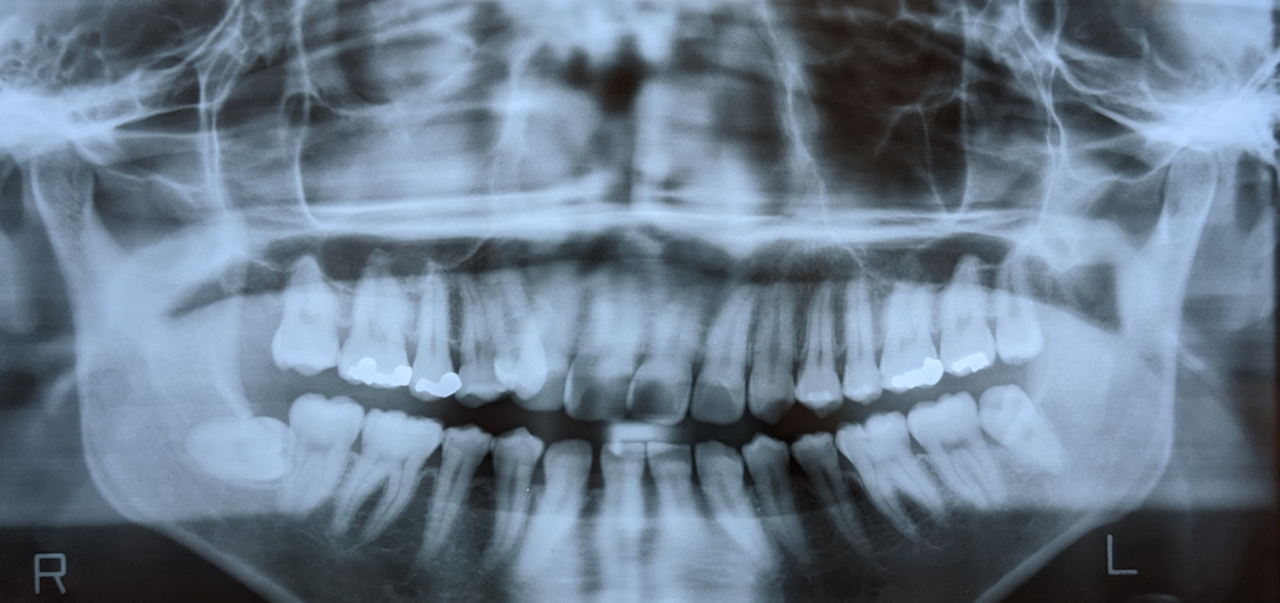

レントゲン検査

インプラント治療は、あごの骨に人工歯根を埋め込む治療なので、あごの骨の状態を確認することも大切です。

ご希望の方には別途費用はかかりますが、レントゲン検査も行います。

目に見えないあごの骨の様子がわかるため、

• インプラントができる状態なのか

• 他に必要な治療がないか

• 治療費や治療期間

といったことを、より詳細にご案内できます。